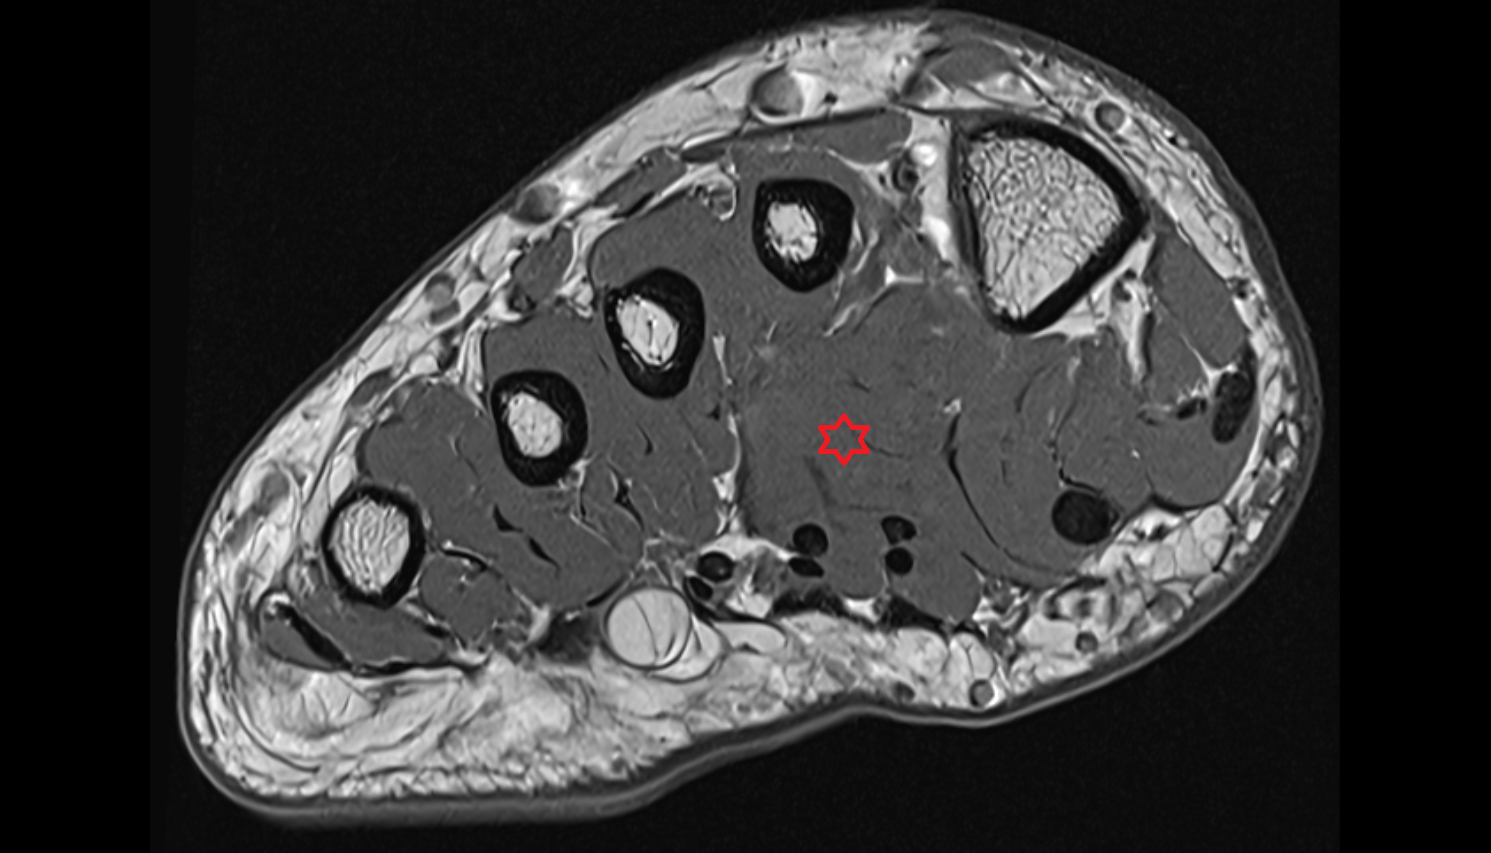

- Plantar aponeurosis